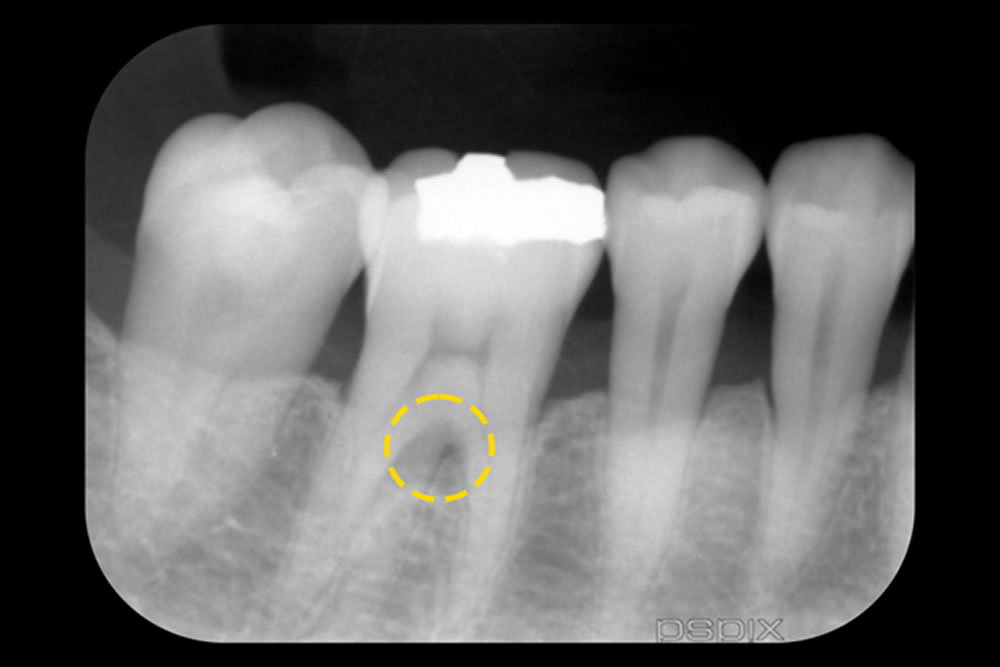

精密根管治療・歯周組織再生療法で重度歯周病を改善した症例 治療前 治療後 こちらの患者さまは、右下の奥歯(第2大臼歯)に歯の根の内部(神経)と歯の周囲の組織(歯周組織)の両方に問題がある複雑な状態でした。治療は、まず根の […]